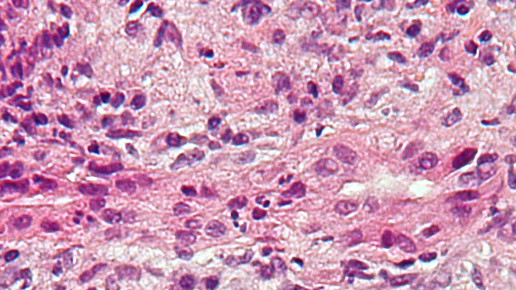

Bestimmte Leberwerte können Aufschluss über die Funktionsfähigkeit der Leber und Hepatozyten geben. Hinweise zu Störungen in den Leberzellen können unter anderem die Alanin-Aminotransferase (ALAT), Aspartat-Aminotransferase (ASAT) und γ-Glutamyltransferase (Gamma-GT) und der Eisenwert geben. Bilirubin, Alkalische Phosphatase, Gesamt-, LDL- und HDL-Cholesterin können als Indikatoren für Unstimmigkeiten in der Ausscheidungsleistung dienen. Die Syntheseleistung können über die Thromboplastinzeit, Cholinesterase, Albumin und Gesamteiweiß beurteilt werden. Bestimmte Störungen der metabolischen Leistung sind über den Ammoniak-Wert festzustellen. Häufige Lebererkrankungen sind Hepatitis, Leberzirrhose, Fettleber und Leberkrebs. Auch gibt es autoimmune Lebererkrankungen.